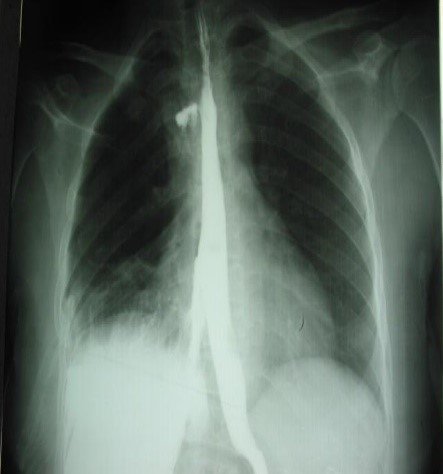

Sepsisli xəstələrdə rentgenoloji müayinədə mediastinumda hava görünməsi yüksək şübhə əlamətidir (Şəkil 9).

Şəkil 9. Mediastinal emfizema